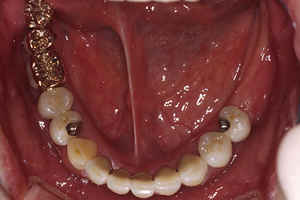

治療後

再評価にて今まで行ってきた治療の経過を確認し、良好な状態であったため、仮歯になっている部分に最終的な被せ物を装着しました。